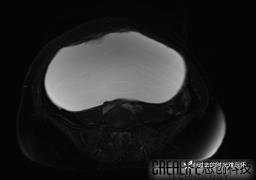

患者性别:女

患者年龄:65岁

主诉: 发现腹部隆起半年余。无其他明显不适。

浆液性囊腺瘤 (22)